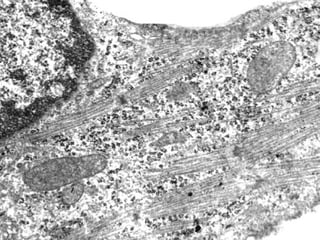

НЕОНАТАЛЬНИЙ КАРДІОМІОЦИТ ЩУРА ПІСЛЯ 24 ГОДИН КУЛЬТИВУВАННЯ

НЕОНАТАЛЬНИЙ КАРДІОМІОЦИТ ЩУРАПІСЛЯ 24 ГОДИН КУЛЬТИВУВАННЯ